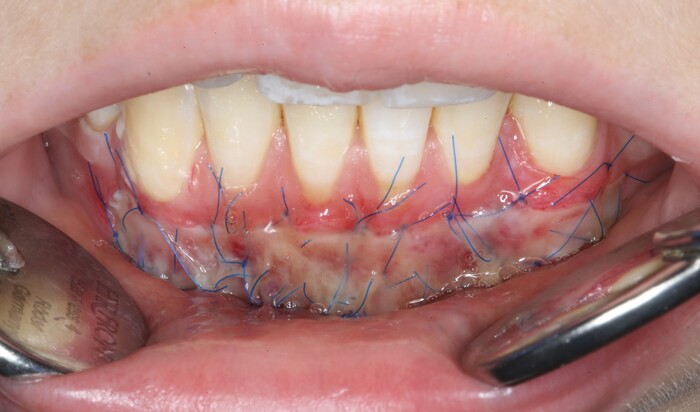

2 – проведение пластики десны.

Был взят трансплантат в области бугра верхней челюсти (это то место, где раньше был зуб мудрости).

Далее проведена пластика десны, снова два месяца ожиданий и установка временной коронки: